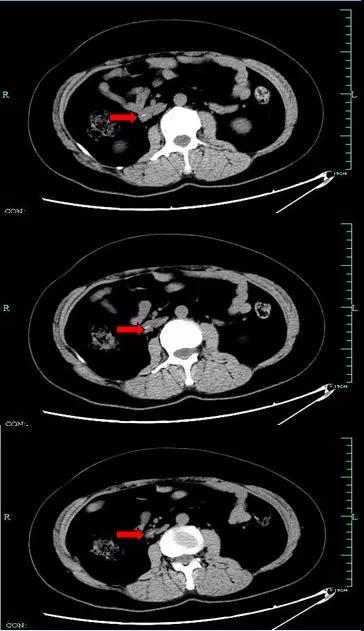

如图 1-3所示:

图 3:腹部 CT 提示十二指肠水平部异物(红色箭头表示异物)